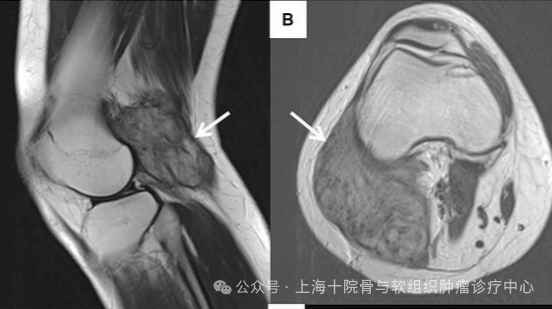

侵襲性纖維瘤,也被稱為硬纖維瘤,是一種罕見且復(fù)雜的腫瘤,屬于結(jié)締組織的良性腫瘤。盡管其良性特性,侵襲性纖維瘤具有局部侵襲性,容易復(fù)發(fā),并且可以對周圍的組織、神經(jīng)和器官造成嚴(yán)重?fù)p害。治療方法的選擇通常取決于腫瘤的大小、位置、進(jìn)展速度以及患者的總體健康狀況。膝關(guān)節(jié)后內(nèi)側(cè)的侵襲性纖維瘤。初診治療由于侵襲性纖維瘤生長、穩(wěn)定與退縮的周期難以預(yù)測,加上手術(shù)和放射治療相關(guān)的顯著并發(fā)癥,使保守觀察等待成為一種合理可行的治療方法。20%~30%的患者在觀察等待中腫瘤出現(xiàn)退縮。退縮可發(fā)生在身體任何部位,其中以腹部較為多見。值得注意的是,觀察等待過程中需對患者進(jìn)行密切的隨訪,觀察等待的前1~2年應(yīng)每3~6月行CT或MRI檢查評估腫瘤有無進(jìn)展。觀察等待策略需在患者充分了解病情的前提下進(jìn)行,有賴于患者充分的理解與配合。腫瘤進(jìn)展之后怎么辦?腹腔外侵襲性纖維瘤進(jìn)展,可采取藥物治療、消融或者栓塞術(shù)、根治性放療,以及手術(shù)。1、外科手術(shù)目前,切除病灶及周圍浸潤組織的外科治療模式仍作為侵襲性纖維瘤的一線治療手段。然而,即使達(dá)到根治性切除要求,AF的局部復(fù)發(fā)率仍然高達(dá)20%~30%。因此,學(xué)者致力于尋找探索AF患者手術(shù)切除術(shù)后復(fù)發(fā)的危險因素。目前,多項(xiàng)研究與共識表明腹外型AF、青年、腫瘤較大、β-catenin突變是公認(rèn)的AF術(shù)后復(fù)發(fā)的危險因素。2、根治性放療根治性放療適用于腹腔外侵襲性纖維瘤。通常情況下,此治療方案適用于不能耐受藥物治療或通過藥物治療不能有效控制情況下的患者,以及手術(shù)風(fēng)險過高或術(shù)后邊緣陽性的患者。根治性放療的推薦劑量為56Gy,分28次照射。在治療時應(yīng)考慮侵襲性纖維瘤浸潤性生長特點(diǎn),類似于高級別軟組織肉瘤。盡管沒有前瞻性數(shù)據(jù),但根治性放療和術(shù)后放療在50-56Gy劑量下似乎有益,術(shù)后標(biāo)準(zhǔn)為1.8-2Gy/次。為放療應(yīng)作為手術(shù)切除后切緣陽性的補(bǔ)充治療,不應(yīng)作為常規(guī)治療手段。3、消融術(shù)或者栓塞術(shù)消融手術(shù):消融,特別是冷凍消融,被推薦作為治療侵襲性纖維瘤的主要模式。它可以為進(jìn)展性的、致死性的或癥狀性的侵襲性纖維瘤提供良好的局部控制和良好的臨床反應(yīng)率。在冷凍消融在技術(shù)上不可行的情況下,如特定的腹部以外侵襲性纖維瘤,可以考慮使用藥物釋放微球(DEB)化療栓塞作為備選方案。4、藥物治療藥物治療是侵襲性纖維瘤的另一種重要方法,尤其適用于那些無法手術(shù)或放射治療效果不佳的病例。目前有幾類藥物在治療侵襲性纖維瘤中顯示出了效果,包括非甾體抗炎藥(NSAIDs)、抗激素藥物(如他莫昔芬)以及新型的靶向藥物。國內(nèi)可獲取的靶向藥物包括索拉非尼、伊馬替尼,以及培唑帕尼。伊馬替尼的總體反應(yīng)率僅為10%~23%,僅可作為挽救治療。化療方案包括甲氨喋呤聯(lián)合長春瑞濱或者長春花堿,脂質(zhì)體阿霉素,多柔比星聯(lián)合或者不聯(lián)合達(dá)卡巴嗪。侵襲性纖維瘤的藥物治療。多學(xué)科的綜合治療在很多情況下,單一的治療方法并不能完全控制侵襲性纖維瘤,因此綜合治療成為一種趨勢。綜合治療包括手術(shù)、放療、藥物治療的聯(lián)合應(yīng)用,以期最大限度地抑制腫瘤生長,減少復(fù)發(fā),改善患者的生活質(zhì)量。進(jìn)展期侵襲性纖維瘤的治療方法多種多樣,包括手術(shù)、放射治療、藥物治療、化療及其聯(lián)合治療等。選擇何種治療方法,需要綜合考慮腫瘤的具體情況、患者的身體狀況及其對不同治療的反應(yīng)。多學(xué)科團(tuán)隊(duì)的協(xié)作和長期的隨訪監(jiān)控對于改善預(yù)后、降低復(fù)發(fā)風(fēng)險具有重要意義。更多骨與軟組織腫瘤、骨轉(zhuǎn)移癌相關(guān)問題,請至上海市第十人民醫(yī)院骨與軟組織腫瘤診療中心就診咨詢。骨科張春林主任專家門診(每周一下午,門診5105診室),張春林主任特需門診(每周四上午,門診5408診室)骨科吳衛(wèi)平主任專家門診(每周三上午,門診5114診室)?!豆悄[瘤骨病》??崎T診,每周一、三、五上午,門診樓2樓2110診室?!扼w表腫物、骨與軟組織腫瘤》專病門診,每周一、三、五上午,門診樓2樓2110診室